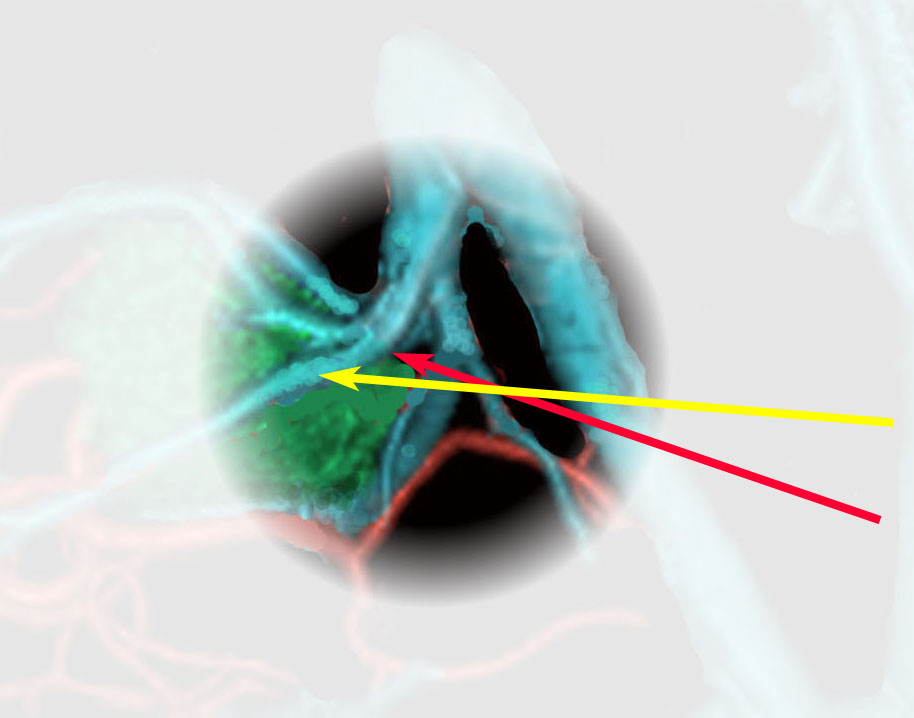

実際に見る静脈はこの領域です。図の説明は側方から見ていますが,手術では腹臥位で後頭極方向からみます。ですから,黄色の矢印の視軸でローゼンタール静脈を見るので,ローゼンタール静脈は術野の深いところに沈んで行くように見えます。同様に赤の矢印でICVを見ますから,ICVも深く沈んで行くように走行して行くように見えます。従って,両静脈を剥離して行くと手術操作野は深く深くなります。